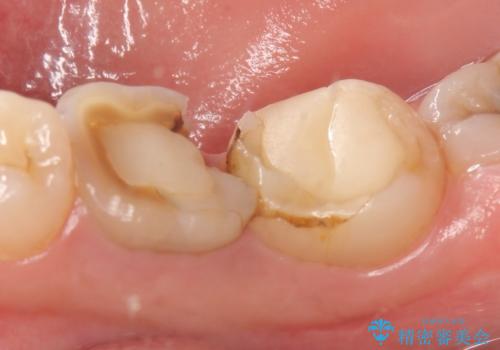

- 奥歯が欠けてしまったので診て欲しいといらっしゃった方の症例です。

再根管治療終了後、オールセラミッククラウンによる補綴を行いました。